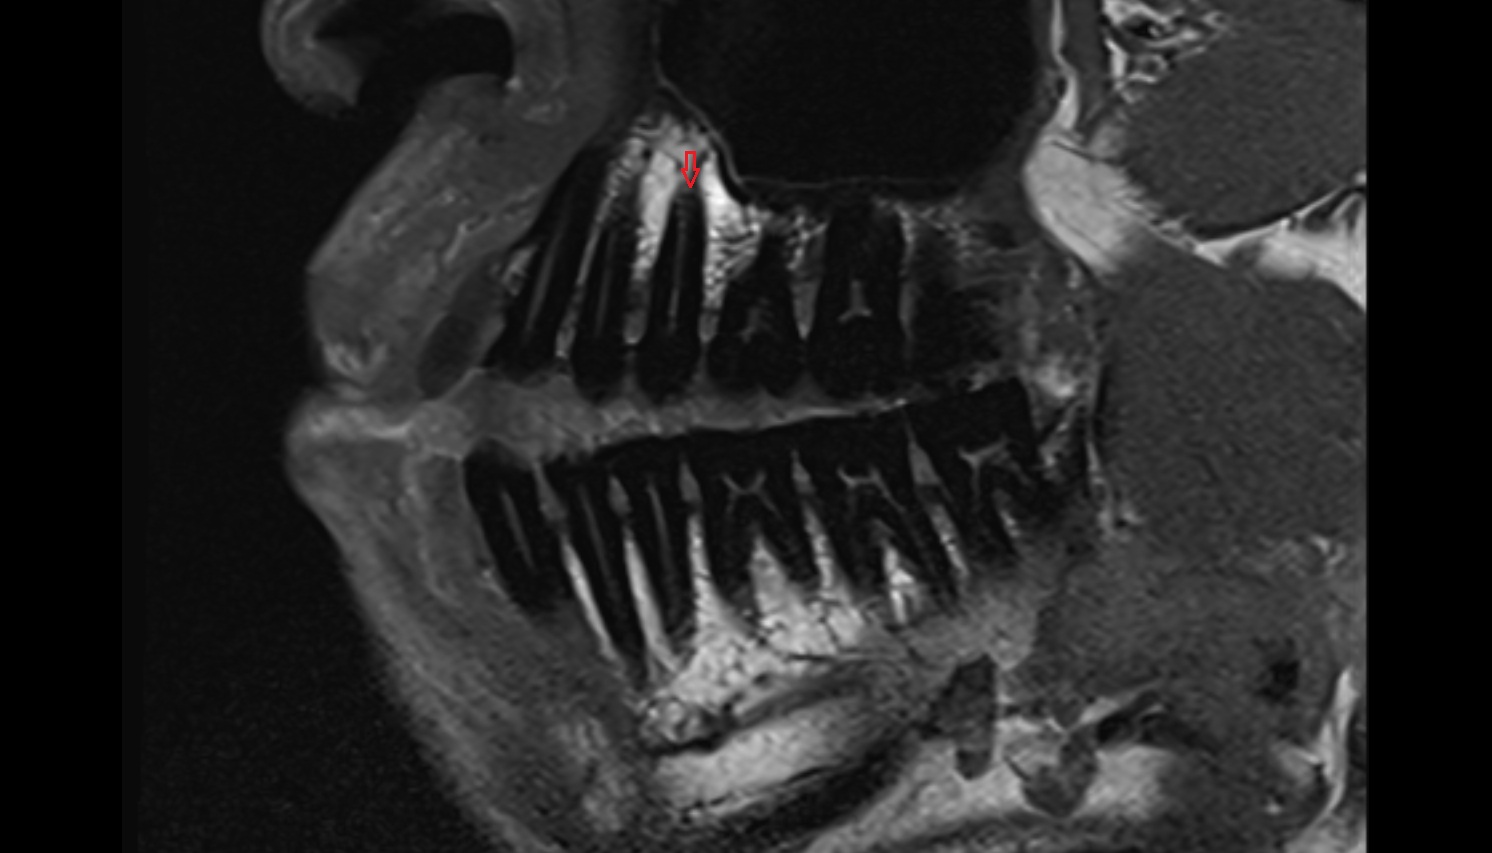

- Central superior incisor tooth

- superior canine tooth

- Superior first molar tooth

- Superior first premolar tooth

- Superior second molar tooth

- Superior second premolar tooth

- Superior third molar tooth

- Anterior superior alveolar nerve